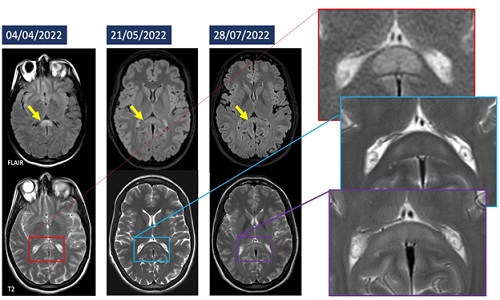

Brain CT scan was unremarkable. MRI showed an oval-shaped, ill-defined lesion hyperintense in T2w and DWI, without enhancement after gadolinium injection in T1w images, in the splenium of corpus callosum, which was swollen [2].

At discharge, the patient displayed balance and subjective visual disturbances (Figure 1). Follow-up MRI showed a reduction in lesion size, although MR spectroscopy showed a decrease in metabolites levels in the splenium compared to the genu of CC (Figure 2).

Figure 1: Balance and subjective visual disturbances of the patient.